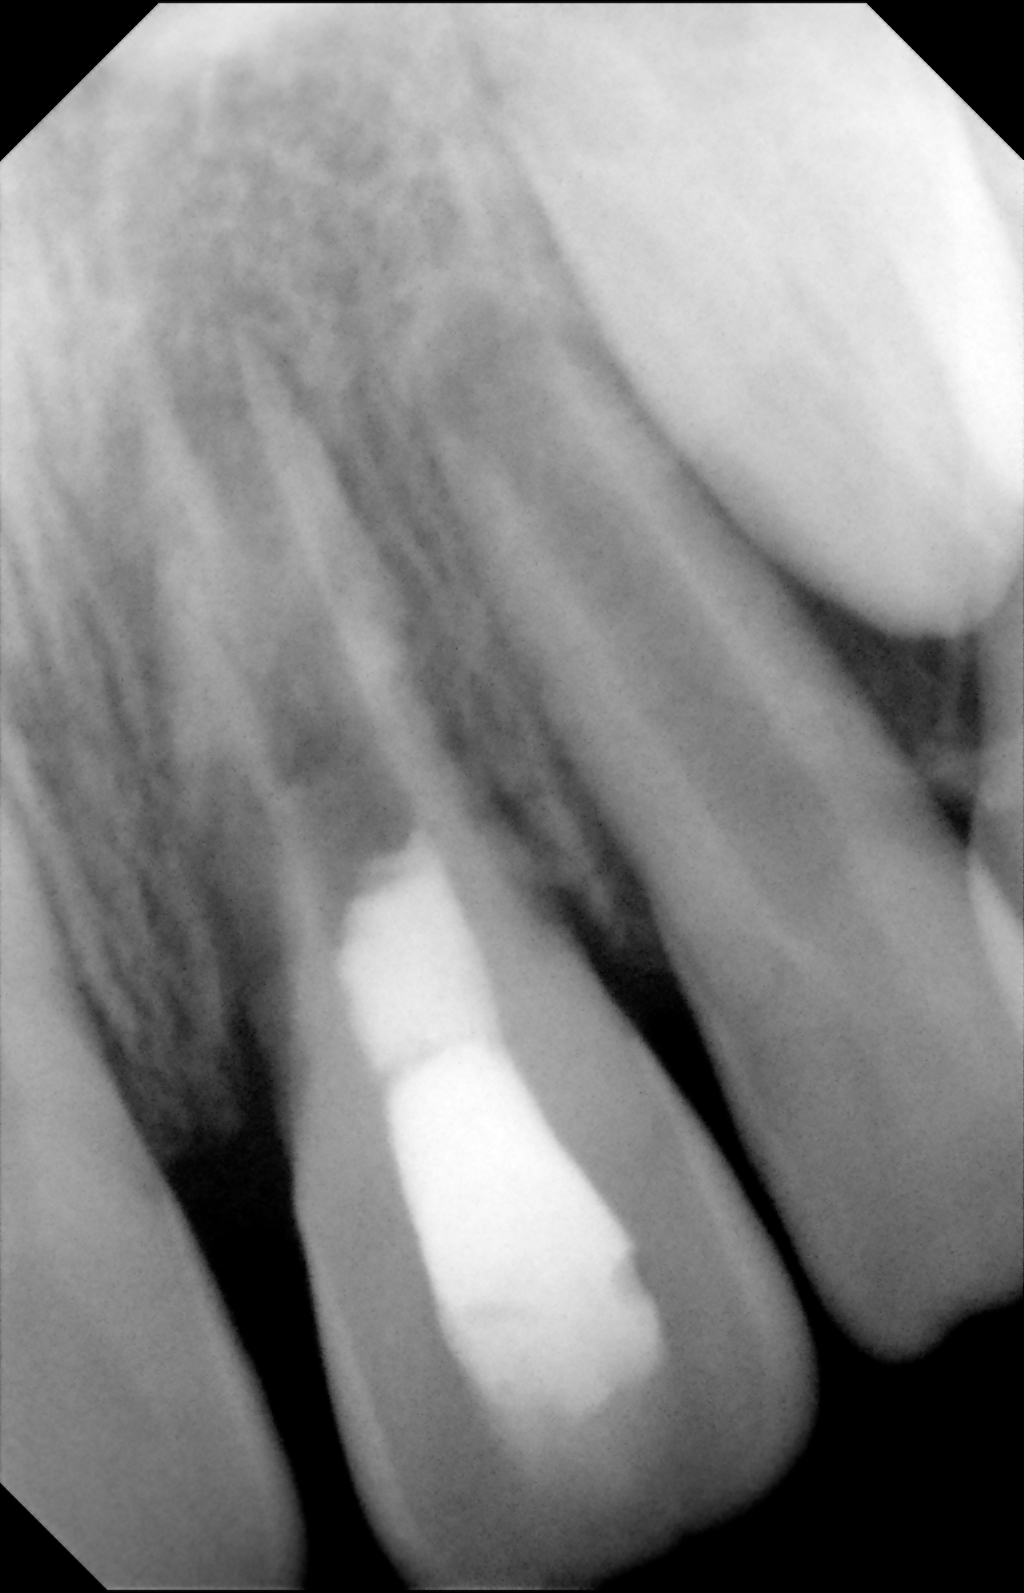

Fig 4. Preoperative radiograph showing aggressive external root resorption and thin dentinal walls.

Figure 4

Clinical procedure: Regeneration of the endodontic pulp space is indicated for cases with very thin dentinal walls and an open apex that is more than 1 mm in diameter radiographically (Figure 4). Disinfection of the root canal system is performed using sodium hypochlorite irrigation followed by a triple antibiotic paste dressing that is left in place for 1 week. At the second visit, ethylenediaminetetraacetic acid (EDTA) is used to condition the dentin walls, which results in the release of growth factors, and bleeding is stimulated in the periapical tissues (where stem cells are located), with the aim of filling the pulp space with a stable blood clot, which would serve as the scaffold. MTA is then placed at the canal orifice in contact with the clot to protect it from coronal microleakage (Figure 5 and Figure 6). In time, the clot should be replaced with a reparative tissue of variable composition, and the root walls should continue to thicken due to the deposition of a dentin-like material on the pre-existing root dentin27,28 (Figure 7 and Figure 8).